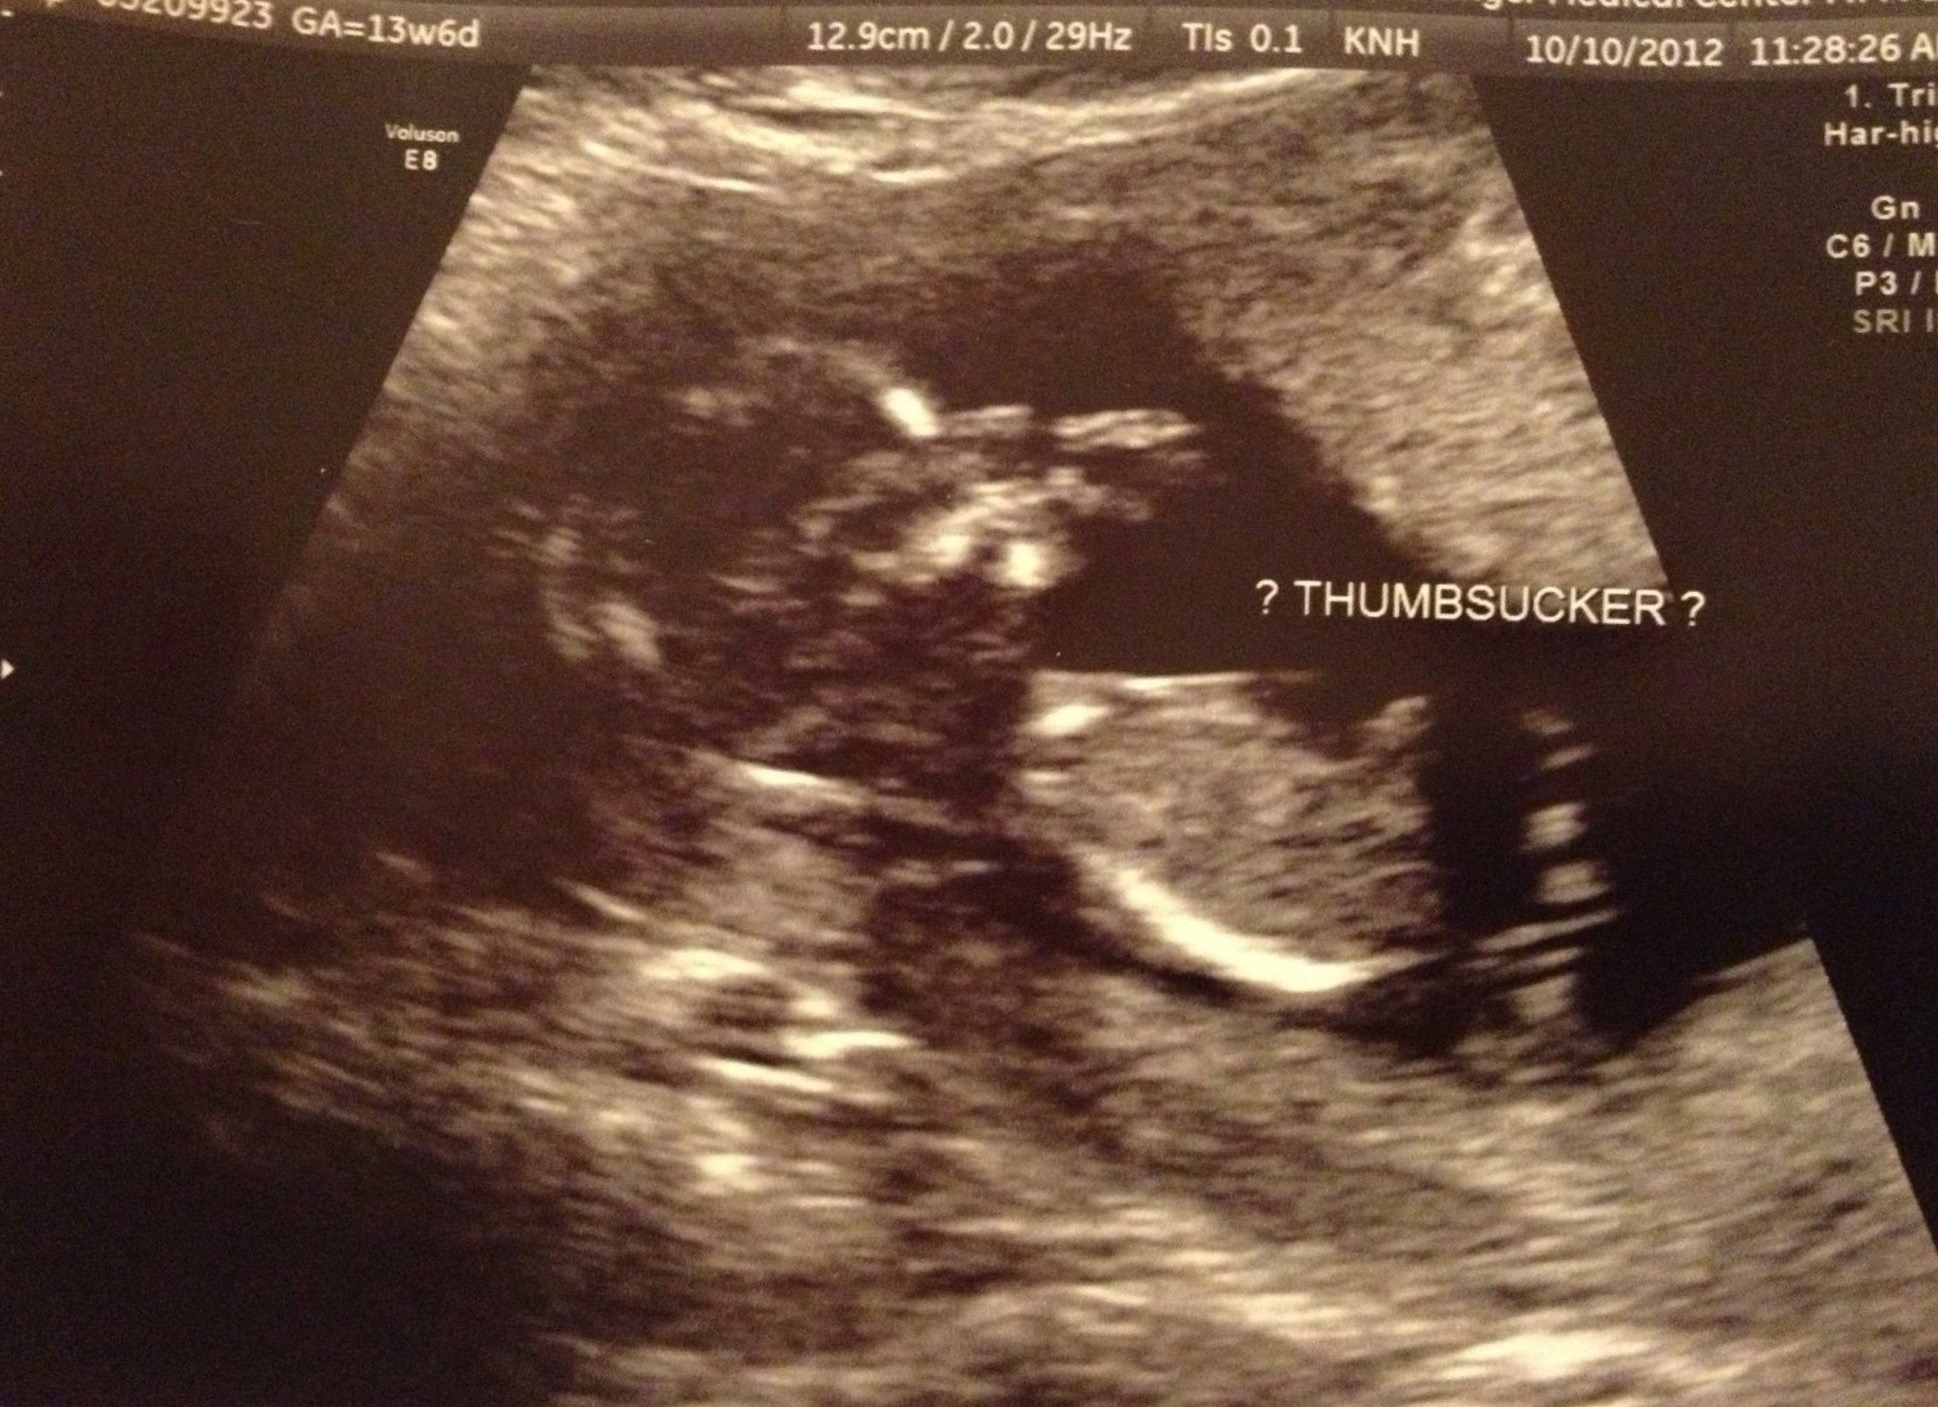

Hi all! I should preface this question with a little information - This is my first pregnancy, and I worry A LOT. Like, everything makes me anxious. I had a great 10 week ultrasound yesterday which put my mind at ease, but then I got my referral for my nuchal translucency US, which gave me something new to worry about!

Anyway, I understand this screening needs to take place between 11-14 weeks. The soonest they are able to get me in is at 13 weeks, 4 days. Clearly this is within the 14 weeks, but I can't help but wish they could see me sooner. I was told that after 14 weeks, the screening is far less reliable in detecting potential issues.